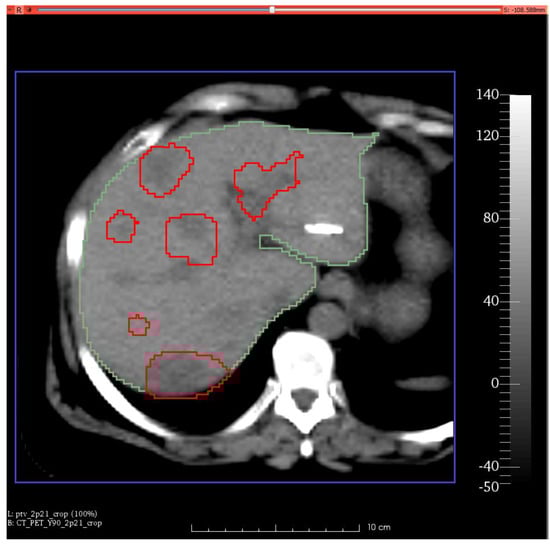

3.2. Patient Studies

Correlation and Agreement between Absorbed Dose Distributions Derived from Spect and Pet Images